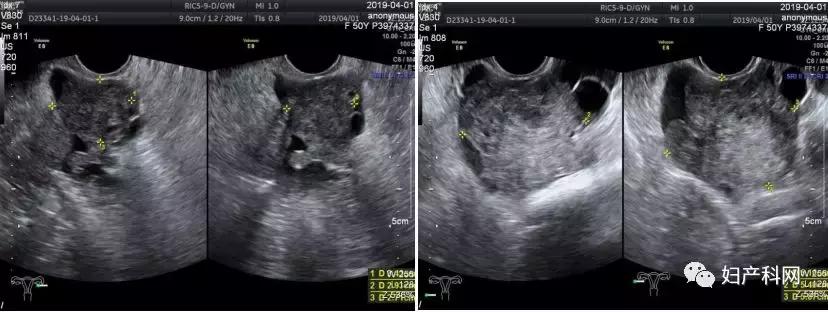

半年余前(2018-8)患者当地医院查腹部超声提示:双侧卵巢增大伴回声改变(右侧大小约6.0*4.9cm,左侧大小约5.6*3.4cm),建议进一步检查,排除占位可能。当时患者无腹痛、腹胀,无恶心、呕吐,无异常阴道流血、排液,无渐进性消瘦等不适,未予重视,未进一步检查。6天前(2019-3-26)患者再次至该院复查腹部超声提示:盆腔内子宫后方可见范围约9.5*5.0*5.8cm的囊实性团(卵巢来源?),腹腔积液;查血CA125 239.5U/ml,CA199 47.57U/ml,CA153 131.40U/ml,考虑盆腔包块持续存在,性质不明,且肿瘤指标异常,建议手术。为求进一步诊治,今患者至我院就诊,复查盆腔超声提示:右附件区见5.2*5.4*5.9cm不均低回声包块,血流较丰富,RI=0.66;左附件区见3.4*2.9*2.7cm低回声,内见散在血流,周边见少许卵巢组织,其表面另见4.0*4.1*3.0cm囊性块,内液清,直肠窝液体深6.1cm(见图1);复查CA125 206U/ml, CA199 57.3U/ml,CA153 156.7U/ml。

图1